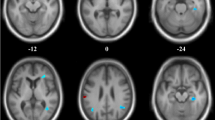

To identify the CBF pattern for AD, we applied SSM/PCA analysis to the MRI CBF maps from the AD and NC groups. Focusing on the major source of variance in the CBF maps, we initially restricted the multiple regression model to include the subject expression scores from the first 6 SSM principal components (PC). The model that included PC1and PC2 (variance accounted for 22.13% and 13.07%, and regression coefficient β = − 0.822 and − 0.569, respectively) was the best for distinguishing patients with AD from NCs. An ADRP was produced by a linear combination of these two PCs, accounting for 25.64% of the total subject × voxel variance. Figure 1 shows the topography of the ADRP that was reliable at P < 0.001 based on the bootstrapping algorithm (1000 iterations) and characterized by relatively negative weights in the bilateral middle and posterior cingulate and precuneus, bilateral inferior parietal lobule, and bilateral middle frontal gyrus, along with relatively positive weights in bilateral putamen and a few frontal areas. The locations of all brain regions and coordinates for voxels with local minimal and maximal weights for this ADRP are shown in Table 2.

Regional topographies of ADRP measured with ASL MRI. The ADRP was identified by combining PC1 and PC2 from SSM/PCA in AD patients and NCs in the identification cohort. Cool color indicates regions with decreased loading, and warm color indicates regions with increased loading. The pattern was overlaid onto a standard MRI brain template to display voxels that were reliable at P < 0.001 based on the bootstrapping algorithm. MCC middle cingulate cortex, PCC posterior cingulate cortex

We noted the topographic similarity between regional loadings provided by SSM/PCA and perfusion differences revealed by SPM (cf. Figures 1 and 3). This is expected given that subject expression score of the ADRP is simply a summed product between the ADRP topography and an individual CBF image such that the greater the similarity between the ADRP and the CBF map, the higher the subject expression score in each AD patient [24]. Although relative CBF value in various regions had a high accuracy in distinguishing AD patients from NCs, subject expression score of the ADRP showed stronger and more extensive correlations with clinical variables, such as cognitive performance, in AD patients in this study. Of note, relative CBF values in this study were measured in spherical volumes of interest (4 mm radius) centered at the peak voxel of each significant cluster where group differences were maximal. The group differences would be smaller in conventional analytical methods owing to signal dilution from lower-intensity voxels when CBF values were measured over the entire cluster detected by SPM or the neuroanatomic structure defined on MRI. Because computation of pattern expression score is performed automatically without clinical information, this approach is more objective than diagnostic categorization achieved by visual interpretation or predefined region of interest (ROI) analysis [24]. Network analysis generally recovers more disease-specific, widely distributed brain regions that may not have direct biological correlates, whereas regional analysis is closer to the diagnostic process based on visual reading of clinical images [37]. According to our present results, it might be beneficial to combine the imaging markers obtained with these two complementary approaches to further improve the diagnosis and evaluation for AD.